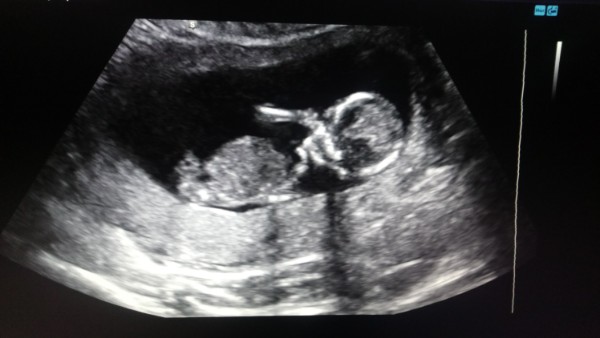

А вот мой мальчик на таком же сроке)

Kristina

Так-то карапуз там танцевал на узи! Видимо когда я попросила фото, то он принял позу)))